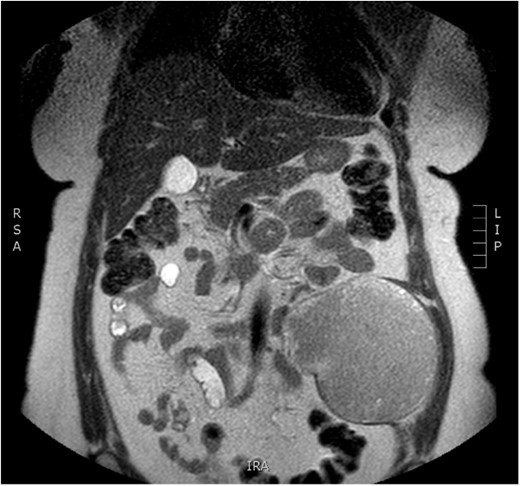

Physical examination revealed a painless, mobile parietal mass on the left anterior abdominal wall, more prominent during cough, of ~13 cm in diameter, with smooth contour and without skin involvement. Laboratory examination including cancer marks showed results within normal limits; hydatid serology (IgG antibodies) was also negative. As ultrasonography results were inconclusive, further imaging with magnetic resonance imaging (MRI) revealed a sizable cystic mass measuring 10 × 13.4 × 11.7 cm, located in the left anterior abdominal quadrant, in the paraumbilical region, between the left internal oblique and the transversus oblique muscle, with projection to the inferior surface of the rectus abdominis. The mass was characterized as a thin-walled cystic lesion, with delayed uptake of intravenous contrast of the wall. High signal intensity was observed on T1-weighted images and low signal intensity on T2-weighted images, with high probability of neoplasia or bleeding (Figs 1–3). No other abdominal or pulmonary lesions were present.

Preoperative MRI—axial plane. T1 weighted image. High sign density of the lesion.